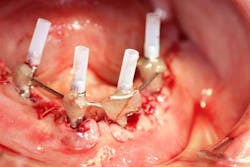

The maxillary arch was indexed first as there was support from the palate to reference position (anterior/posterior) (figure 20). Then the lower was put into position to gain proper vertical dimension and occlusion. It, too, was then indexed; both upper and lower were given to the lab technician to start the conversion process. Next, impression copings were placed (one arch at a time) and secured with paperclips; a full-arch PVS impression was taken and likewise sent to the lab (figures 21-23). Finally, after the conversion process was completed, the bridges were secured in place on the multiunit abutments, torqued to 15nCm, and covered. Bite was adjusted and follow-up care was arranged (figures 24-26).